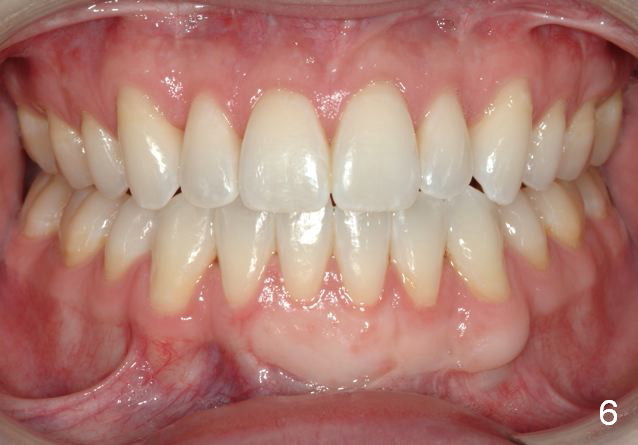

Final photos are taken on 03/23/2016. Mid face deficiency improved, now just a hint (Fig.3). Before (Fig.4,10) and after (Fig.5-9) occlusal adjustment of the canines.

BTW: Philip reports a life changing event! Why? Not just because he can chew his food better and has improved appearance, but he can breathe as a result of maxillary expansion and advancement. He said that his only regret was that he did not correct it sooner;-) He had seen allergists, ENTs, and pulmonologists prior to orthodontics and surgery.